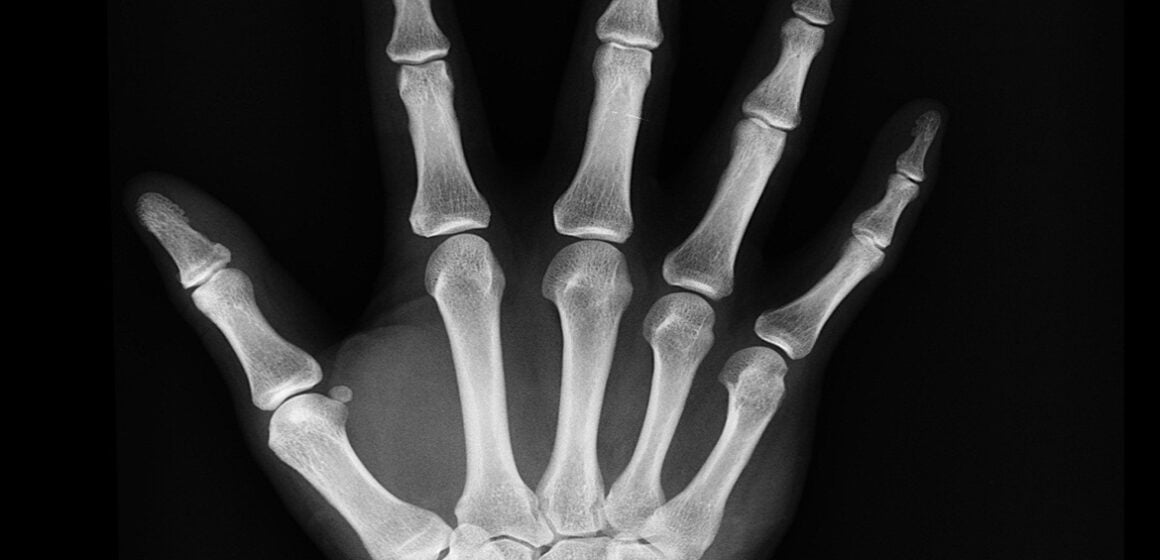

Falaram de William, do Grêmio, que quebrou um dedo, e alguém disse que os chineses ‘teriam’ (falou assim, que teriam) descoberto um jeito de colar ossos com uma cola instantânea.

Pois não é fake news. A notícia está em todos os jornais. É um produto que permite que as partes fraturadas sejam coladas sem a necessidade de placas e parafusos.

É claro que deve ser respeitado o tempo de regeneração e consolidação da área com fratura. Mas é um avanço para a ortopedia.